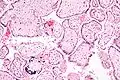

![]() Микрофотография плацентарной инфекции (плацентарный ЦМВ) | |

Микрофотография цитомегаловирусного плацентита.